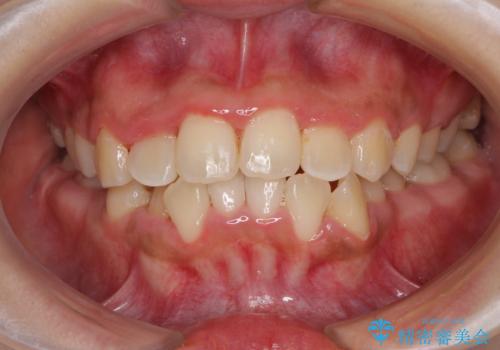

前後に重なった前歯 ワイヤー装置と急速拡大装置を併用したインビザライン矯正

- 前歯の著しい叢生とクロスバイトを気にして来院された患者様です。

叢生が強いため、一見すると抜歯矯正と判断したくなりますが、下顎臼歯が舌側に倒れていることから、上顎骨を側方拡大し、非抜歯矯正の可能性を検討することとしました。

非抜歯矯正が可能となった場合には、インビザラインにて矯正治療を行うこととしました。

急速拡大装置による上顎骨の側方拡大が思った以上にうまくいき、非抜歯での矯正が可能となりました。

内側に倒れていた下顎の臼歯は起き上がり、清掃性も大幅に改善されました。